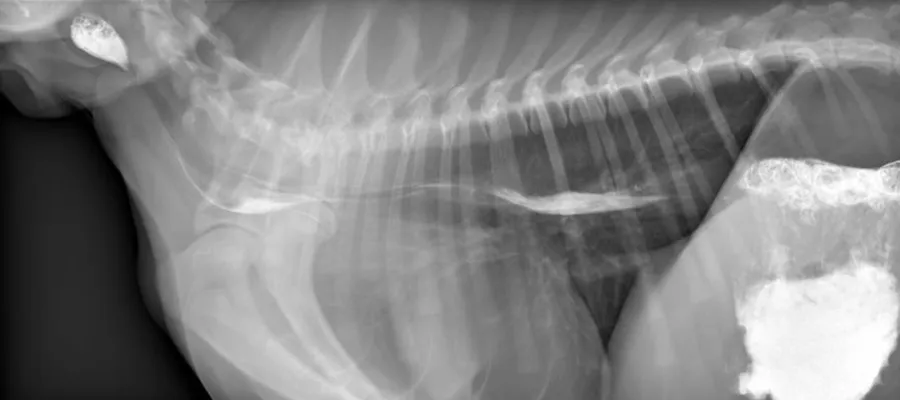

Still image/ radiograph of a dog \"swallowing study\". Contrast medium appears white as it moves from the mouth (left side of the image) through the food pipe and ends up in the stomach (right side of image)

In addition, we can perform radiography in “real time”, which is called dynamic digital radiography (also known as fluoroscopy). This allows us to visualise certain processes as they happen in the patients. This approach is particularly valuable during the evaluation of dogs and cats with swallowing difficulties (dysphagia), regurgitation or other signs of oesophageal disorders.